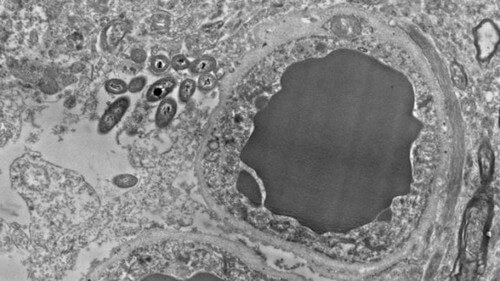

L’aspetto curioso di tutta la questione è che gli astrociti sembrano essere la sede preferita dei batteri intestinali che vivono nel cervello.

Tanto nel primo studio quanto in quello parallelo, è stata osservata la presenza di batteri nel cervello, umano e delle cavie, in situazioni non infettive e non traumatiche. Il microbioma cerebrale si trova soprattutto nella substantia nigra, nell’ippocampo e nella corteccia prefrontale e in scarse quantità nello striato. Nessuno dei cervelli esaminati mostrava segni di infiammazione.

Immagine principale per gentile concessione di Rosalia Roberts, Courtney Walker e Charlene Farmer.